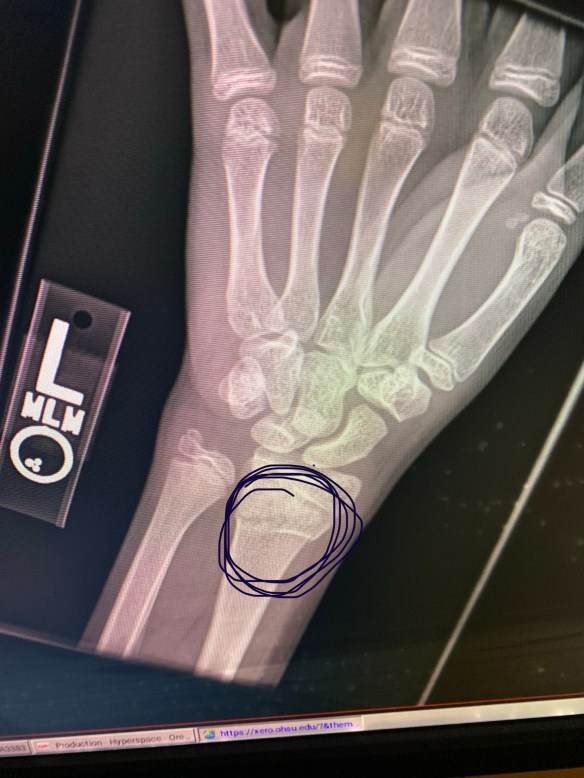

Buckle fracture of his wrist.